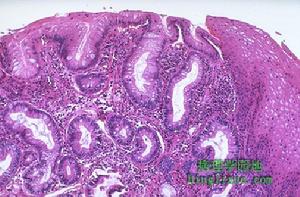

(1)肌病性假性腸梗阻(內臟肌病):病變主要在腸壁平滑肌,可分家族性或散發性。其主要病理變化是腸壁環行肌或縱行肌的退行性變,以後者為甚。有時肌肉完全萎縮,並被膠原代替。(2)神經病性假性腸梗阻(內臟神經病):病變主要在腸壁肌肉間神經叢的神經,可為散發性或家族性。1969年Dyer等報導發現其病理變化主要發生在腸壁肌間神經叢,表現為神經元和神經元突起的退行性變和腫脹,有些病例尚有神經系統的其他部分受累。(3)乙醯膽鹼受體功能缺陷性假性腸梗阻:無肌肉或神經的器質性異常發現,但生理試驗測定有腸運動功能的異常。1981年bannister等報導1例假性腸梗阻,經組織切片檢查未發現有肌肉或神經疾病的組織學變化,認為該病例的發生可能與腸平滑肌的毒蕈鹼乙醯膽鹼受體功能的缺陷有關。

其中以系統性硬化症致慢性假性腸梗阻為多見,其主要病理變化為腸壁平滑肌萎縮和纖維化,又以環行肌的病變為甚;澱粉樣變性可見腸壁肌層內有大量澱粉沉積;黏液性水腫腸壁肌層有黏液性水腫物質;糖尿病在腸壁肌肉和肌間神經叢常無明顯改變。

實驗室檢查:組織學診斷是本病診斷的重要方法,可明確其病理類型。剖腹探查全層腸壁活檢,所取組織應包括空、迴腸和結腸,且至少2cm2,需行常規HE染色和Smith銀染色。通過直腸活檢亦助診斷。